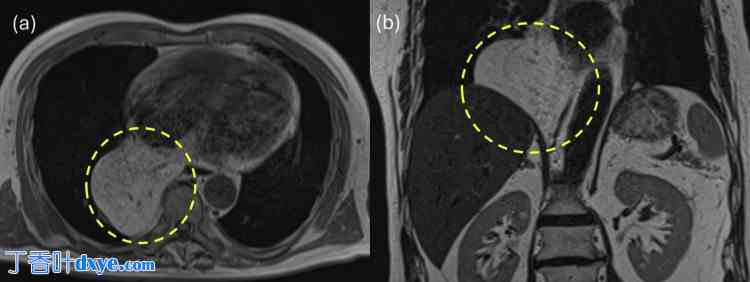

一名79岁的男性患者因胸闷约一个月就诊于当地医院。患者身高169.7 cm,体重70.2 kg。心电图显示心率为65次/分,窦性心律。体格检查未发现胸部和腹部异常。血液检查结果也未发现异常。患者无胃肠道或心血管疾病病史,医生问诊时也未发现腹部或胸部外伤史。然而,患者有糖尿病和血脂异常病史,并定期服药。胸部X光片显示疑似纵隔肿瘤(图1),患者被转诊至呼吸内科。进一步增强MRI(图2)和CT(图3)检查后,由于大网膜血管经食管裂孔延伸至纵隔,怀疑为ITOH,患者被转诊至胃肠外科。患者因症状性疝气接受腹腔镜疝修补术。术中发现食管裂孔右侧为疝口(图 4a),大网膜脱垂至右后纵隔。大网膜未与疝囊粘连,可手法复位至腹腔(图 4b)。

图 2. 增强 MRI。

腹腔内脂肪经食管裂孔脱垂至纵隔。